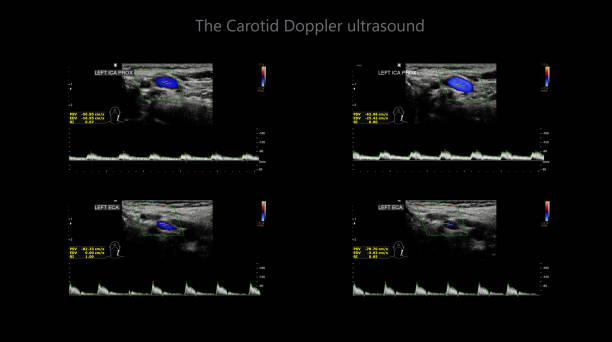

경동맥 초음파 검사로 알수있는병 - 검사 결과 해석

검사 결과를 해석할 때, 의사는 다음 사항을 고려합니다.

- 경동맥의 크기와 형태: 경동맥이 충분히 넓고 매끄럽게 유지되는지 확인합니다.

- 혈류 속도: 혈액이 경동맥을 흐르는 속도를 측정하여 혈액순환에 이상이 없는지 확인합니다.

- 혈액 응고물질의 존재: 콜레스테롤과 혈액 응고물질이 경동맥 벽에 쌓여 있는지 확인합니다.